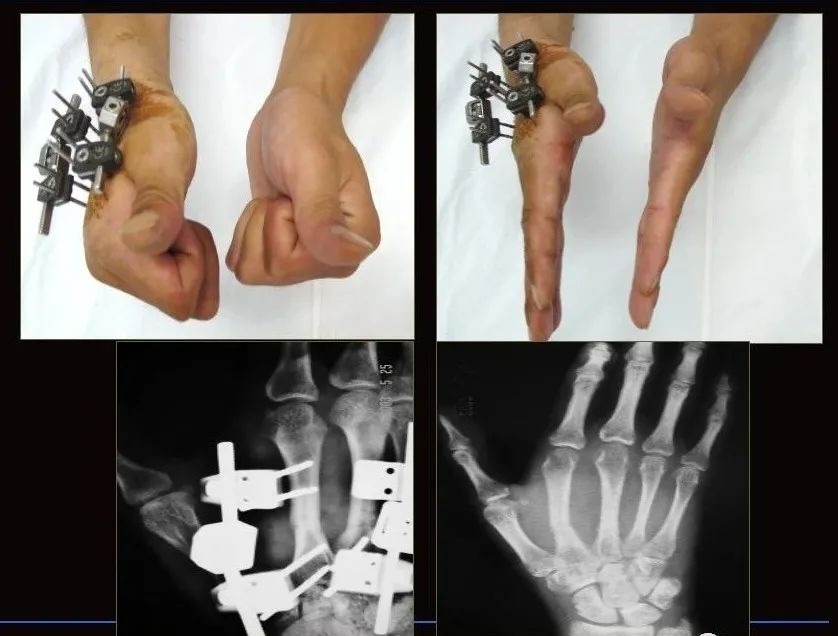

粉碎性掌指骨骨折由于骨支架被破坏,有时手术切开也难以解剖复位或无法坚强内固定。外固定支架使粉碎性骨折在牵引的作用下可恢复并维持其长度,起到相对固定的作用。

不同的骨科外固定支架放置部位不同:第1、2掌指骨放置于桡背侧,第4、5掌指骨放置于尺背侧,第3掌指骨则根据情况适当放置于桡背侧或尺背侧,注意进针点以防损伤肌腱。闭合性骨折可在X线下进行闭合复位,复位不理想时可行小切口切开辅助复位。

对粉碎性骨折无法解剖复位时,可以结合有限内固定,外固定支架可部分复位并维持力线;